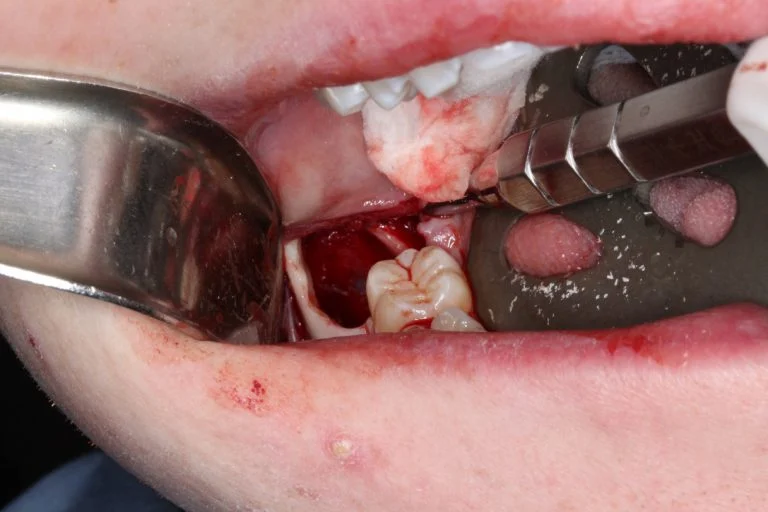

A modified sagittal split-type incision was made in the right mandibular quadrant extending up the external oblique ridge and anterior ramus. A full thickness mucoperiosteal flap was reflected until the proposed site was sufficiently exposed. An 18-gauge needle and syringe were used to aspirate the lesion prior to excavation, which returned straw-colored fluid, confirming this was NOT a vascular lesion. A round bur under copious irrigation was used to unroof the superior aspect of the right mandible until a cystic lining was revealed. A series of straight and angled curettes were used to carefully enucleate the mass from the bony cavity and from the inferior alveolar nerve canal. The lesion was removed in its entirety without perforation of the lining (Figure 2). The residual defect was examined, and the borders were smoothened with a fine bone file and a limited peripheral ostectomy was performed in the distal and buccal aspects of the residual cavity. The distal root of #31 was also scaled thoroughly in the event of residual remnants of the cystic lining arising from a dentigerous origin. The wound was then copiously irrigated with sterile saline and closed in a double layered fashion with resorbable suture material (Figure 3).